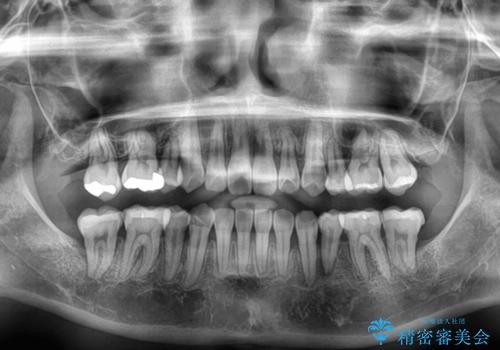

前歯のデコボコが顕著なのはもちろんですが、左右ともに奥歯の咬み合わせに問題があり、上顎臼歯が前方位にある状態でした。

上顎は左右の第一小臼歯2本を、下顎は左右第二小臼歯2本を抜歯することで、奥歯の咬み合わせを改善しながら、デコボコを解消していくこととしました。

奥歯の咬み合わせ改善にはどうしても長期間を要します。

3年強とお伝えしておりましたが、予想通り3年3ヶ月で治療を終えることができました。